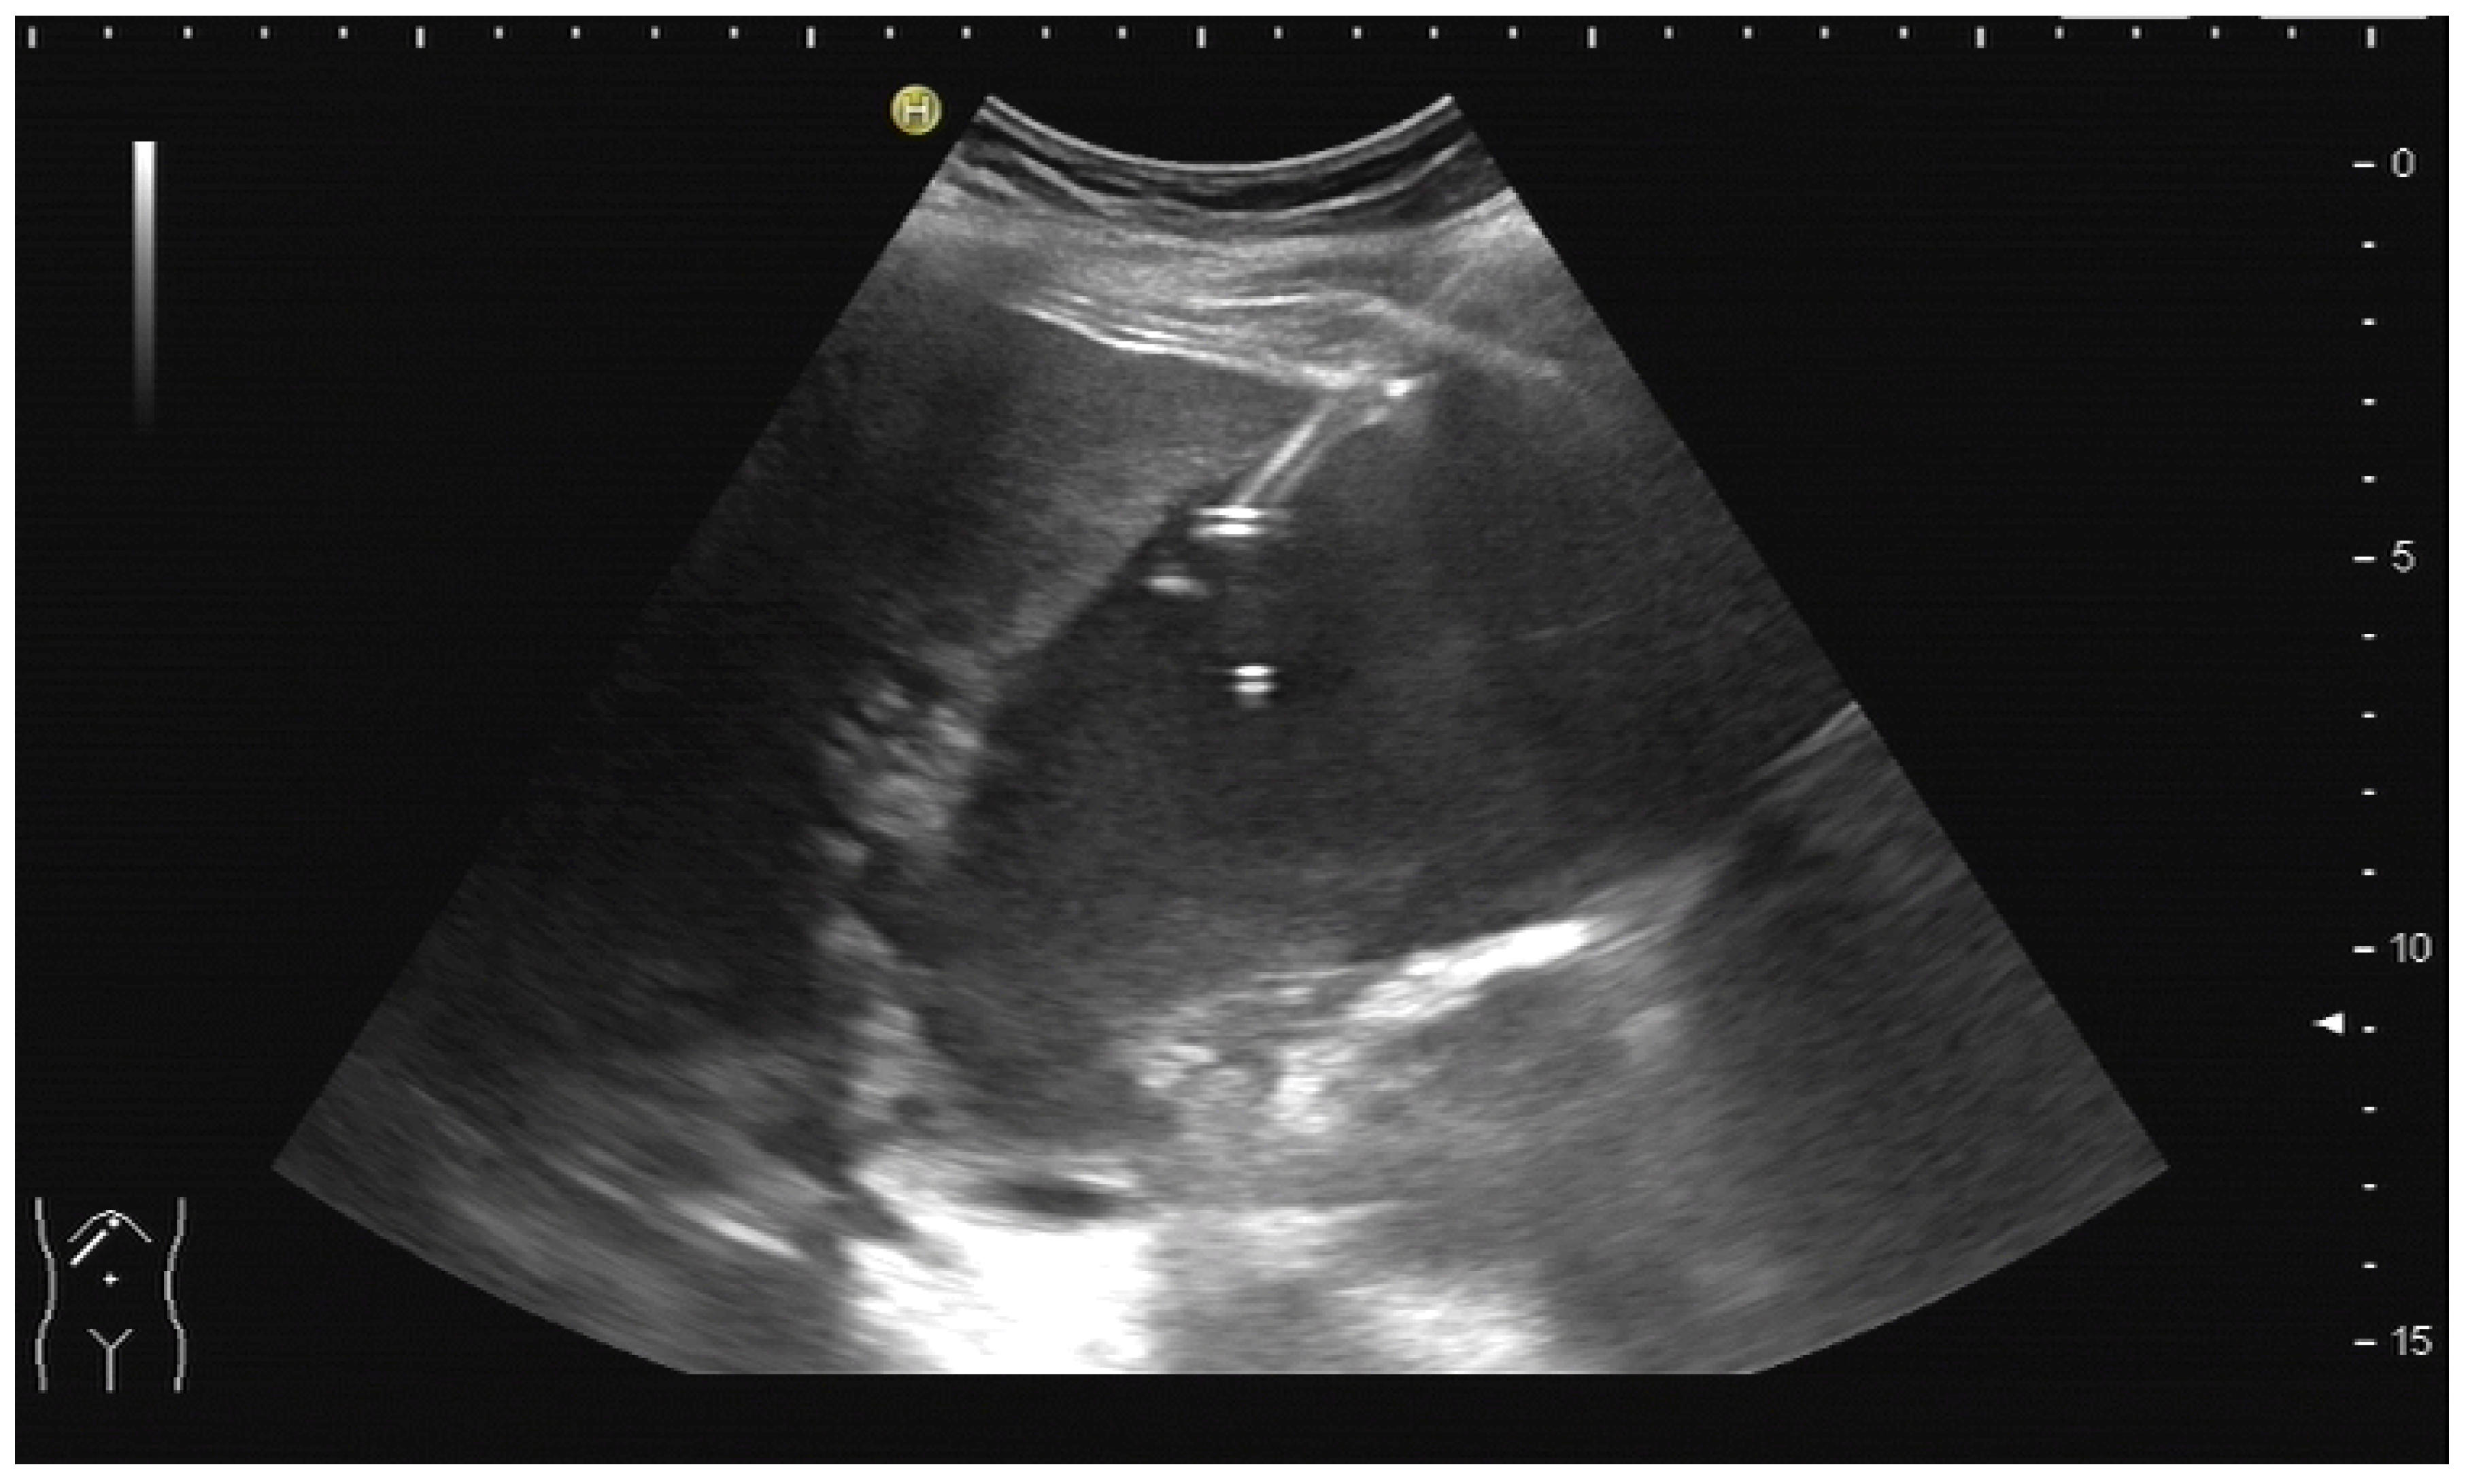

PTBD is commonly performed in the so-called “in plane technique” (Figure 1a,b).

(a) Puncture in plane. The needle is inserted at the centre of the small side of the transducer; (b) Needle tip (yellow arrow), body (white arrows), and target (bile duct) are depicted in one plane. The needle tip is kept in plane by very small movements of the transducer.

The needle is inserted at the narrow side of the transducer and advanced in the US plane. It can thereby be depicted on its whole trajectory. For a successful puncture, the interventionalist has to keep the needle shaft, tip, and target (bile duct) on the image at all times. Losing the tip or the target being out of sight will obviously prohibit a successful puncture. Not having the needle shaft in sight but seeing the tip and target means the further trajectory of the needle will miss the bile duct. Careful tiny corrections, either of the probe orientation or needle direction, must then be undertaken to have all three in sight during the procedure.

In cases of extrahepatic obstruction, mostly the right liver lobe will be addressed. It is common practice to head for the peripheral branches in Segment V (cf. Figure 3a,b), as from there to the common bile duct, the biliary branches form a harmonic arch, and the forward movement of the guide wire seems unpretentious [3]. However, US guidance allows the puncture of any biliary duct of the right or left liver lobe that can be depicted well (Figure 4a–c).

(a) A pointed angle between the needle trajectory and a bile duct of Segment V/VI is given; (b) Puncture of a dilated bile duct in Segment IV at a suitable angle. A guide wire with a bended tip should be used to facilitate the correct advancement; (c) A guide wire is placed in a dilated intrahepatic bile duct in Segment III.

If peripheral bile ducts are not dilated and puncture is difficult, sometimes, targeting the central bile ducts and even the common bile duct close to the hilum are the only options to place drainage. When trying to puncture the common bile duct, it is sensible to enter it as proximal as possible to avoid biliary leakage after drain removal. The needle tract should point towards the distal common bile duct (CBD) to facilitate guide-wire advancement (Figure 5).

Puncture of the CBD in a patient with pancreatic carcinoma. The tip of the needle is seen in the dilated CBD. Pigtail drainage was placed in the CBD, and ten days later, internal drainage by a self-expanding metal stent was placed using a rendezvous technique (percutaneous transpapillary guide-wire advancement and endoscopic stent placement over the wire).